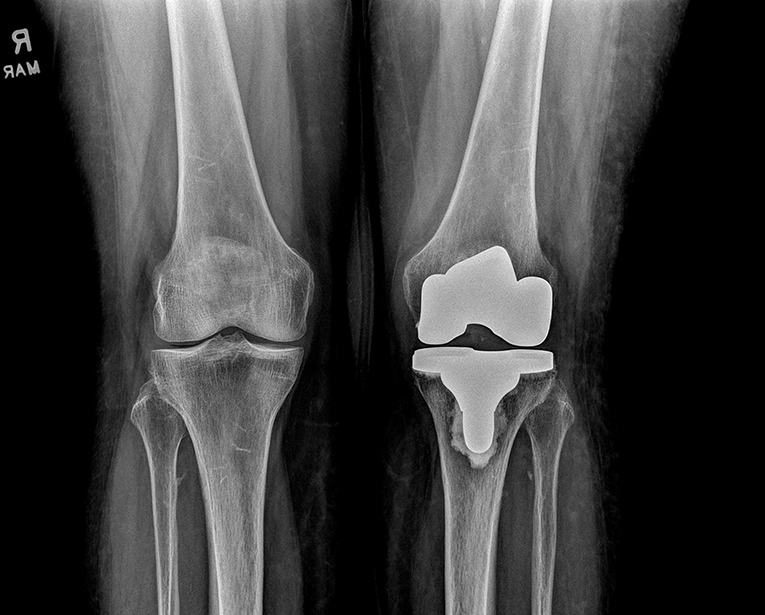

Figure 1: A patient following total knee replacement

Courtesy of Matthew Grosso, MD, FAAOS

“Hip and knee replacements are among the most common orthopaedic procedures, and PJI affects 1-2% of primary hip and knee replacement procedures from hematogenous spread, contiguous spread from a local source, or surgical site infection from the index procedure,” Dr. Grosso said. “These patients also routinely receive dental care, and orthopaedic surgeons and dentists are frequently asked whether and when a patient should receive antibiotics prior to a dental procedure.”